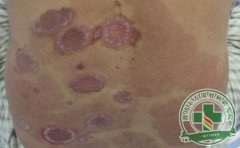

牛皮癣是一种易复发且较为顽固的慢性炎症皮肤病,它给患者的身心健康都带来较大的伤害,因此,牛皮癣患者应该积极的寻求治疗牛皮癣的方法,并且在日常生活中做好护理工作,以减轻牛皮癣带来的负担,那么潍坊治疗牛皮...[详细]